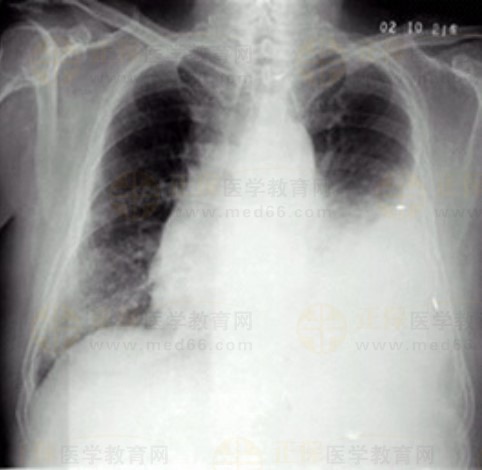

02卷-5.女性,55歲,胸悶、氣短5天,加重1天。診斷

A.右上肺炎

B.左側(cè)胸腔積液

C.左下肺不張

D.左肺癌

本題答案:B

【該題針對(duì)“ X線-胸腔積液 ”知識(shí)點(diǎn)進(jìn)行考核】